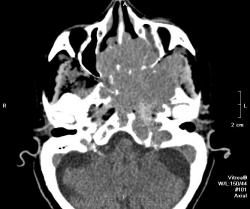

Краниофарингеома? Есть ли данные контрастирования?

Нет, контрастирования не делали. Бабушку отпустили домой, сказали, что опухоль неоперабельная. Вряд ли это краниофарингиома. Скорее это опухоль из основной пазухи или из решеток. У нас она прошла как опухоль основания черепа. Увы!